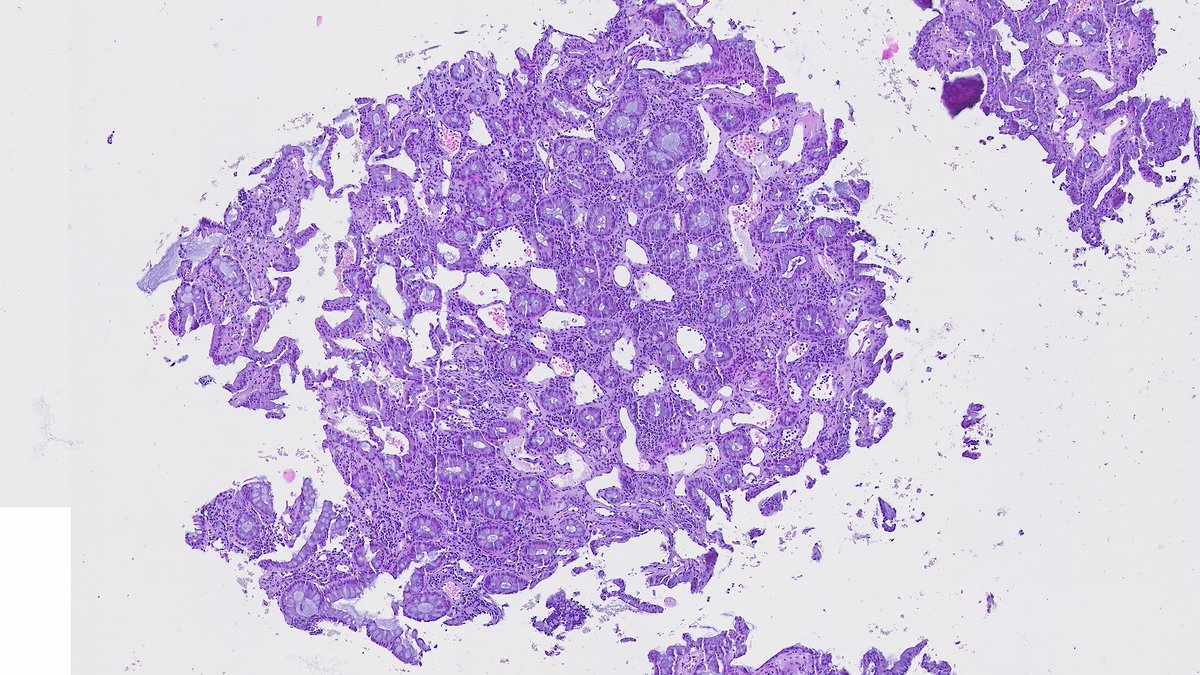

Illustration of a case of Burkitt lymphoma in the intestine with characteristic variable/ patchy SOX11 expression pattern. SOX11 may come in handy in tricky cases when you need more evidence to push for Burkitt lymphoma vs other mimickers #hemepth #lmsm #pathtwitter #PathX #MedX

SibaElHussein's tweet image. Illustration of a case of Burkitt lymphoma in the intestine with characteristic variable/ patchy SOX11 expression pattern. SOX11 may come in handy in tricky cases when you need more evidence to push for Burkitt lymphoma vs other mimickers #hemepth #lmsm #pathtwitter #PathX #MedX